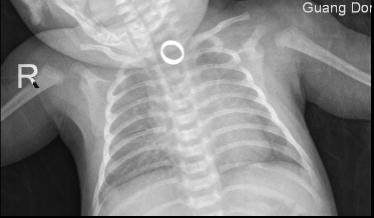

家长们赶紧将可可倒立、拍背、扣喉……使出浑身解数 , 但依旧无济于事 , 只能急急忙忙地将可可送到附近的医院 。 X线检查显示戒指位于食管上段 , 当地医院在尝试了各种方法后 , 仍是没有成功地将卡在可可食管里的戒指取出 。

医院X线检查图 , 考虑异物存留